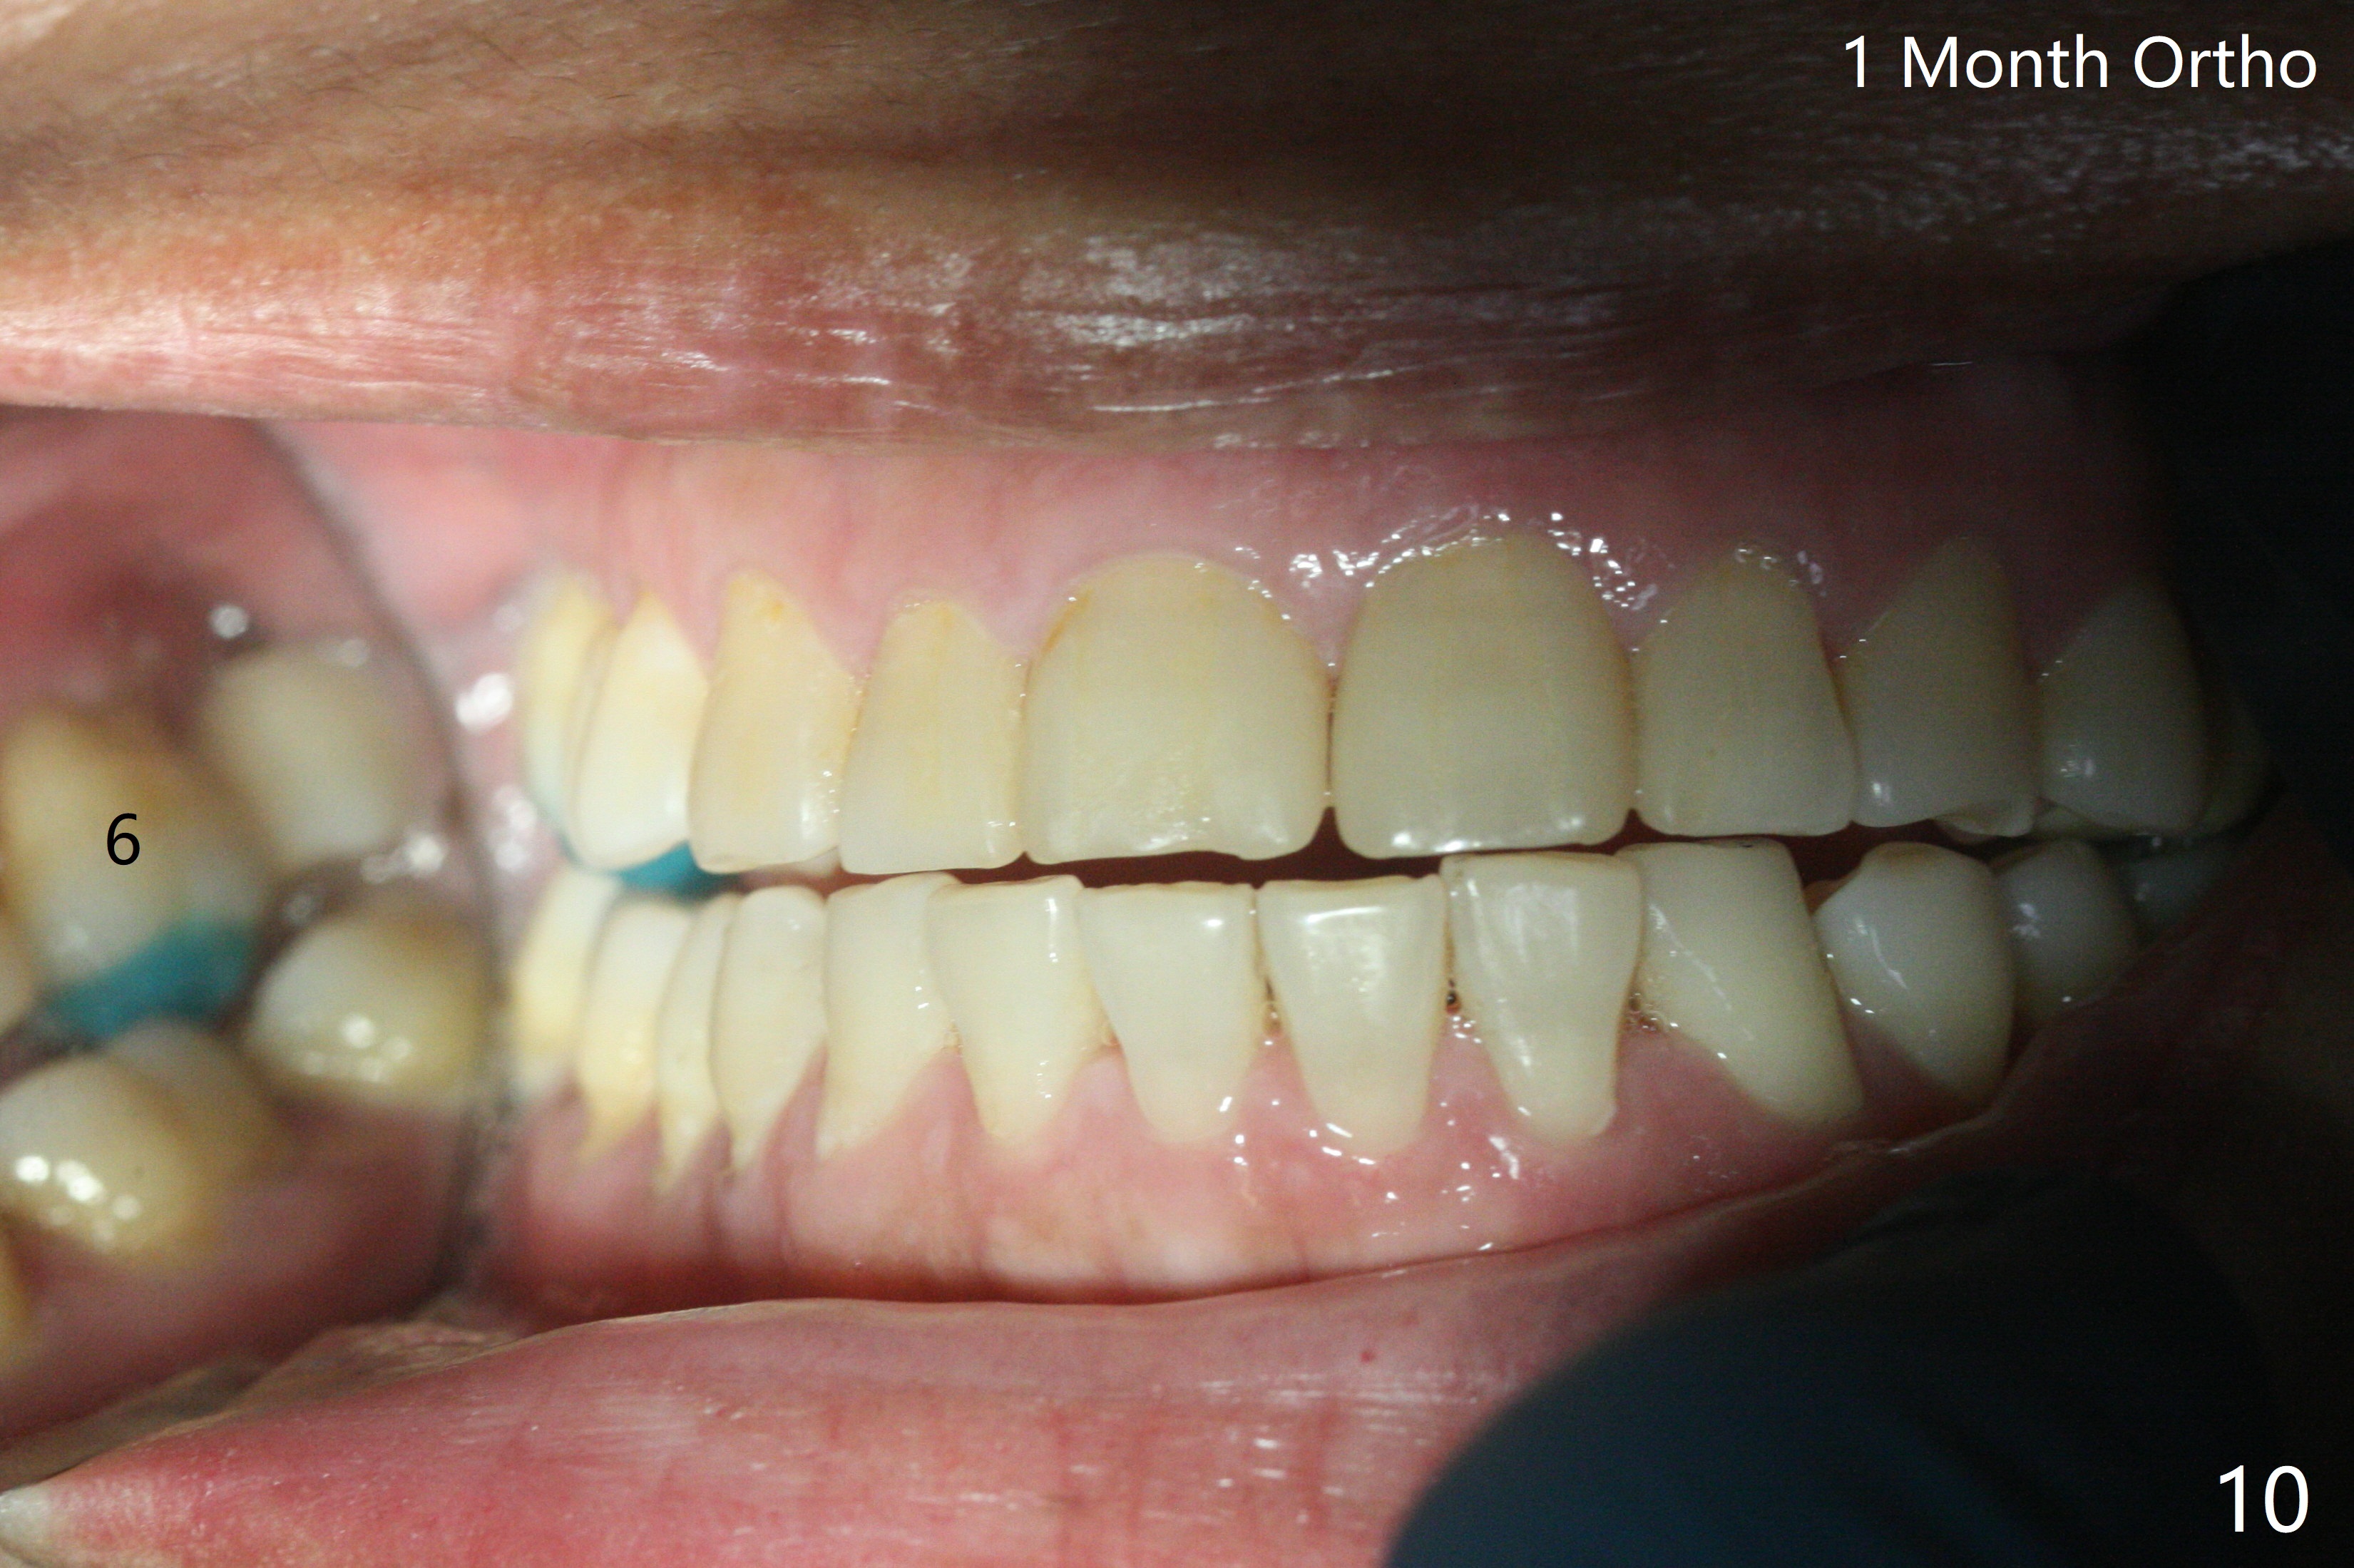

左上六植牙第三次失败后五个月,牙槽嵴宽度尚可,切开后放置导板,3.2乘19毫米园钻头好像接近上颌窦底板(图一),但是粘性骨块和4乘10毫米报废植体就不能进入上颌窦(图二),最后不得不使用3毫米Bicon骨凿,之后同一个报废植体就似乎进入上颌窦(图三),4.5乘8.5毫米正式植体植入深度和稳定性均正常(图四),腭侧植体稍微暴露,放置愈合螺丝后,放置骨粉和PRF膜,缝合,左上5植体放置5.7x4.5(4)毫米基台,固定牙周敷料。术后5.5个月植体好像整合(图五),缺牙间隙特别小,5临时牙冠(P)必须取出才能切开暴露植体,放置5.5x5毫米愈合基台(图六)。伤口愈合后,必须做渐进性负荷,之后做简单局部矫正,推7往远中,6缺失3年,7往近中倾斜移位。两周后牙周敷料脱落,伤口愈合,放置修复基台,故意将基台平面朝远中,足够空间制作临时牙冠(图七)。调整基台长度(比较图七,八)。制作连体牙冠(5,6),有意提高5牙冠高度,使左上7不与对合牙接触,有利于远中移位(图九)。也要在对侧提高咬合(图十)。局部矫正一个月后,磨去右侧咬合垫和磨短左上5,6临时牙冠,前牙还不能完全接触(图十一)。1-2星期前牙开合自行消失,取模做左上5,6牙冠。局部矫正似乎使左上7远中移位大约3毫米(比较图十二,十三)。粘固拧紧后(20 Ncm)14号牙牙冠咬合增高,拍摄根尖片(图十三),两个基台好像仍然完全就位,然后调整咬合。